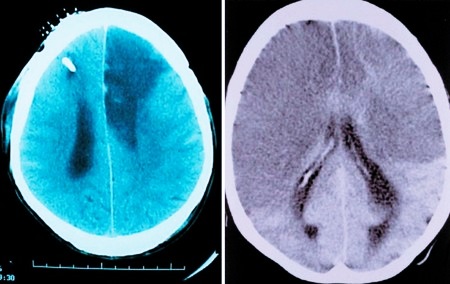

Чтобы верно диагностировать гибель мозга, в стационаре прибегают к инструментальному исследованию:

- энцефалограмме (ЭЭГ);

- контрастному исследованию сосудов мозга;

Для нейронов крайне губительно кислородное голодание, даже если оно не длительное. Буквально после нескольких минут полного отсутствия подачи кислорода ткани начинают гибнуть. Электроэнцефалограмма в этом случае покажет нулевую линию. Это означает, что мозговая активность отсутствует полностью.

При энцефалографии исследуется деятельность мозга. При этом аппарат регистрирует биотоки, их работа воспроизводится на бумаге в форме кривых.

В протокол диагностики также входит исследование сосудов мозга при помощи контрастного вещества. Его не всегда можно выполнить, так как могут быть финансовые ограничения, а иногда просто нет оборудования. Суть теста в том, что вводится контрастное вещество, которое через кровоток попадает в сосуды мозга и выявляет возможные участки некроза. Если мозг умер, то вещество не попадает в его сосуды. Это стопроцентное подтверждение смерти.